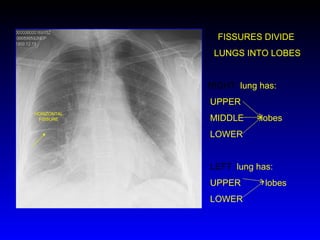

HORIZONTAL FISSURE FISSURES DIVIDE  LUNGS INTO LOBES RIGHT  lung has: UPPER  MIDDLE  lobes LOWER LEFT  lung has: UPPER  lobes LOWER